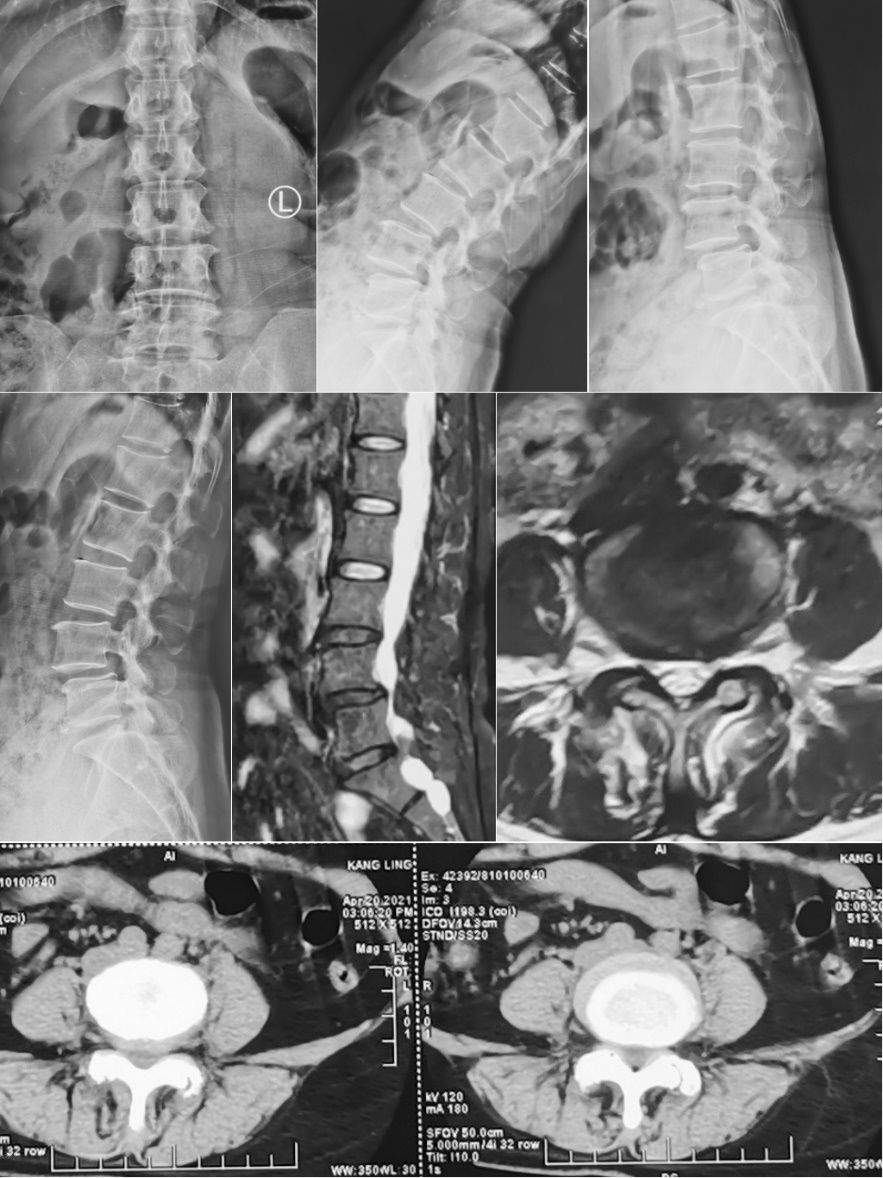

第一例患者女性,73岁,因“腰部反复疼痛20余年,加重伴左下肢疼痛4月”以“腰椎滑脱症(L3、 I°)、腰椎管狭窄症”住院。入院后经术前讨论、评估后制定治疗方案,并与患者及其家属充分沟通,行OLIF手术。术后第二天,患者下地活动,腰痛和左下肢疼痛完全消失,无明显不适,疗效满意。

术前影像

术中

术后复查X线片